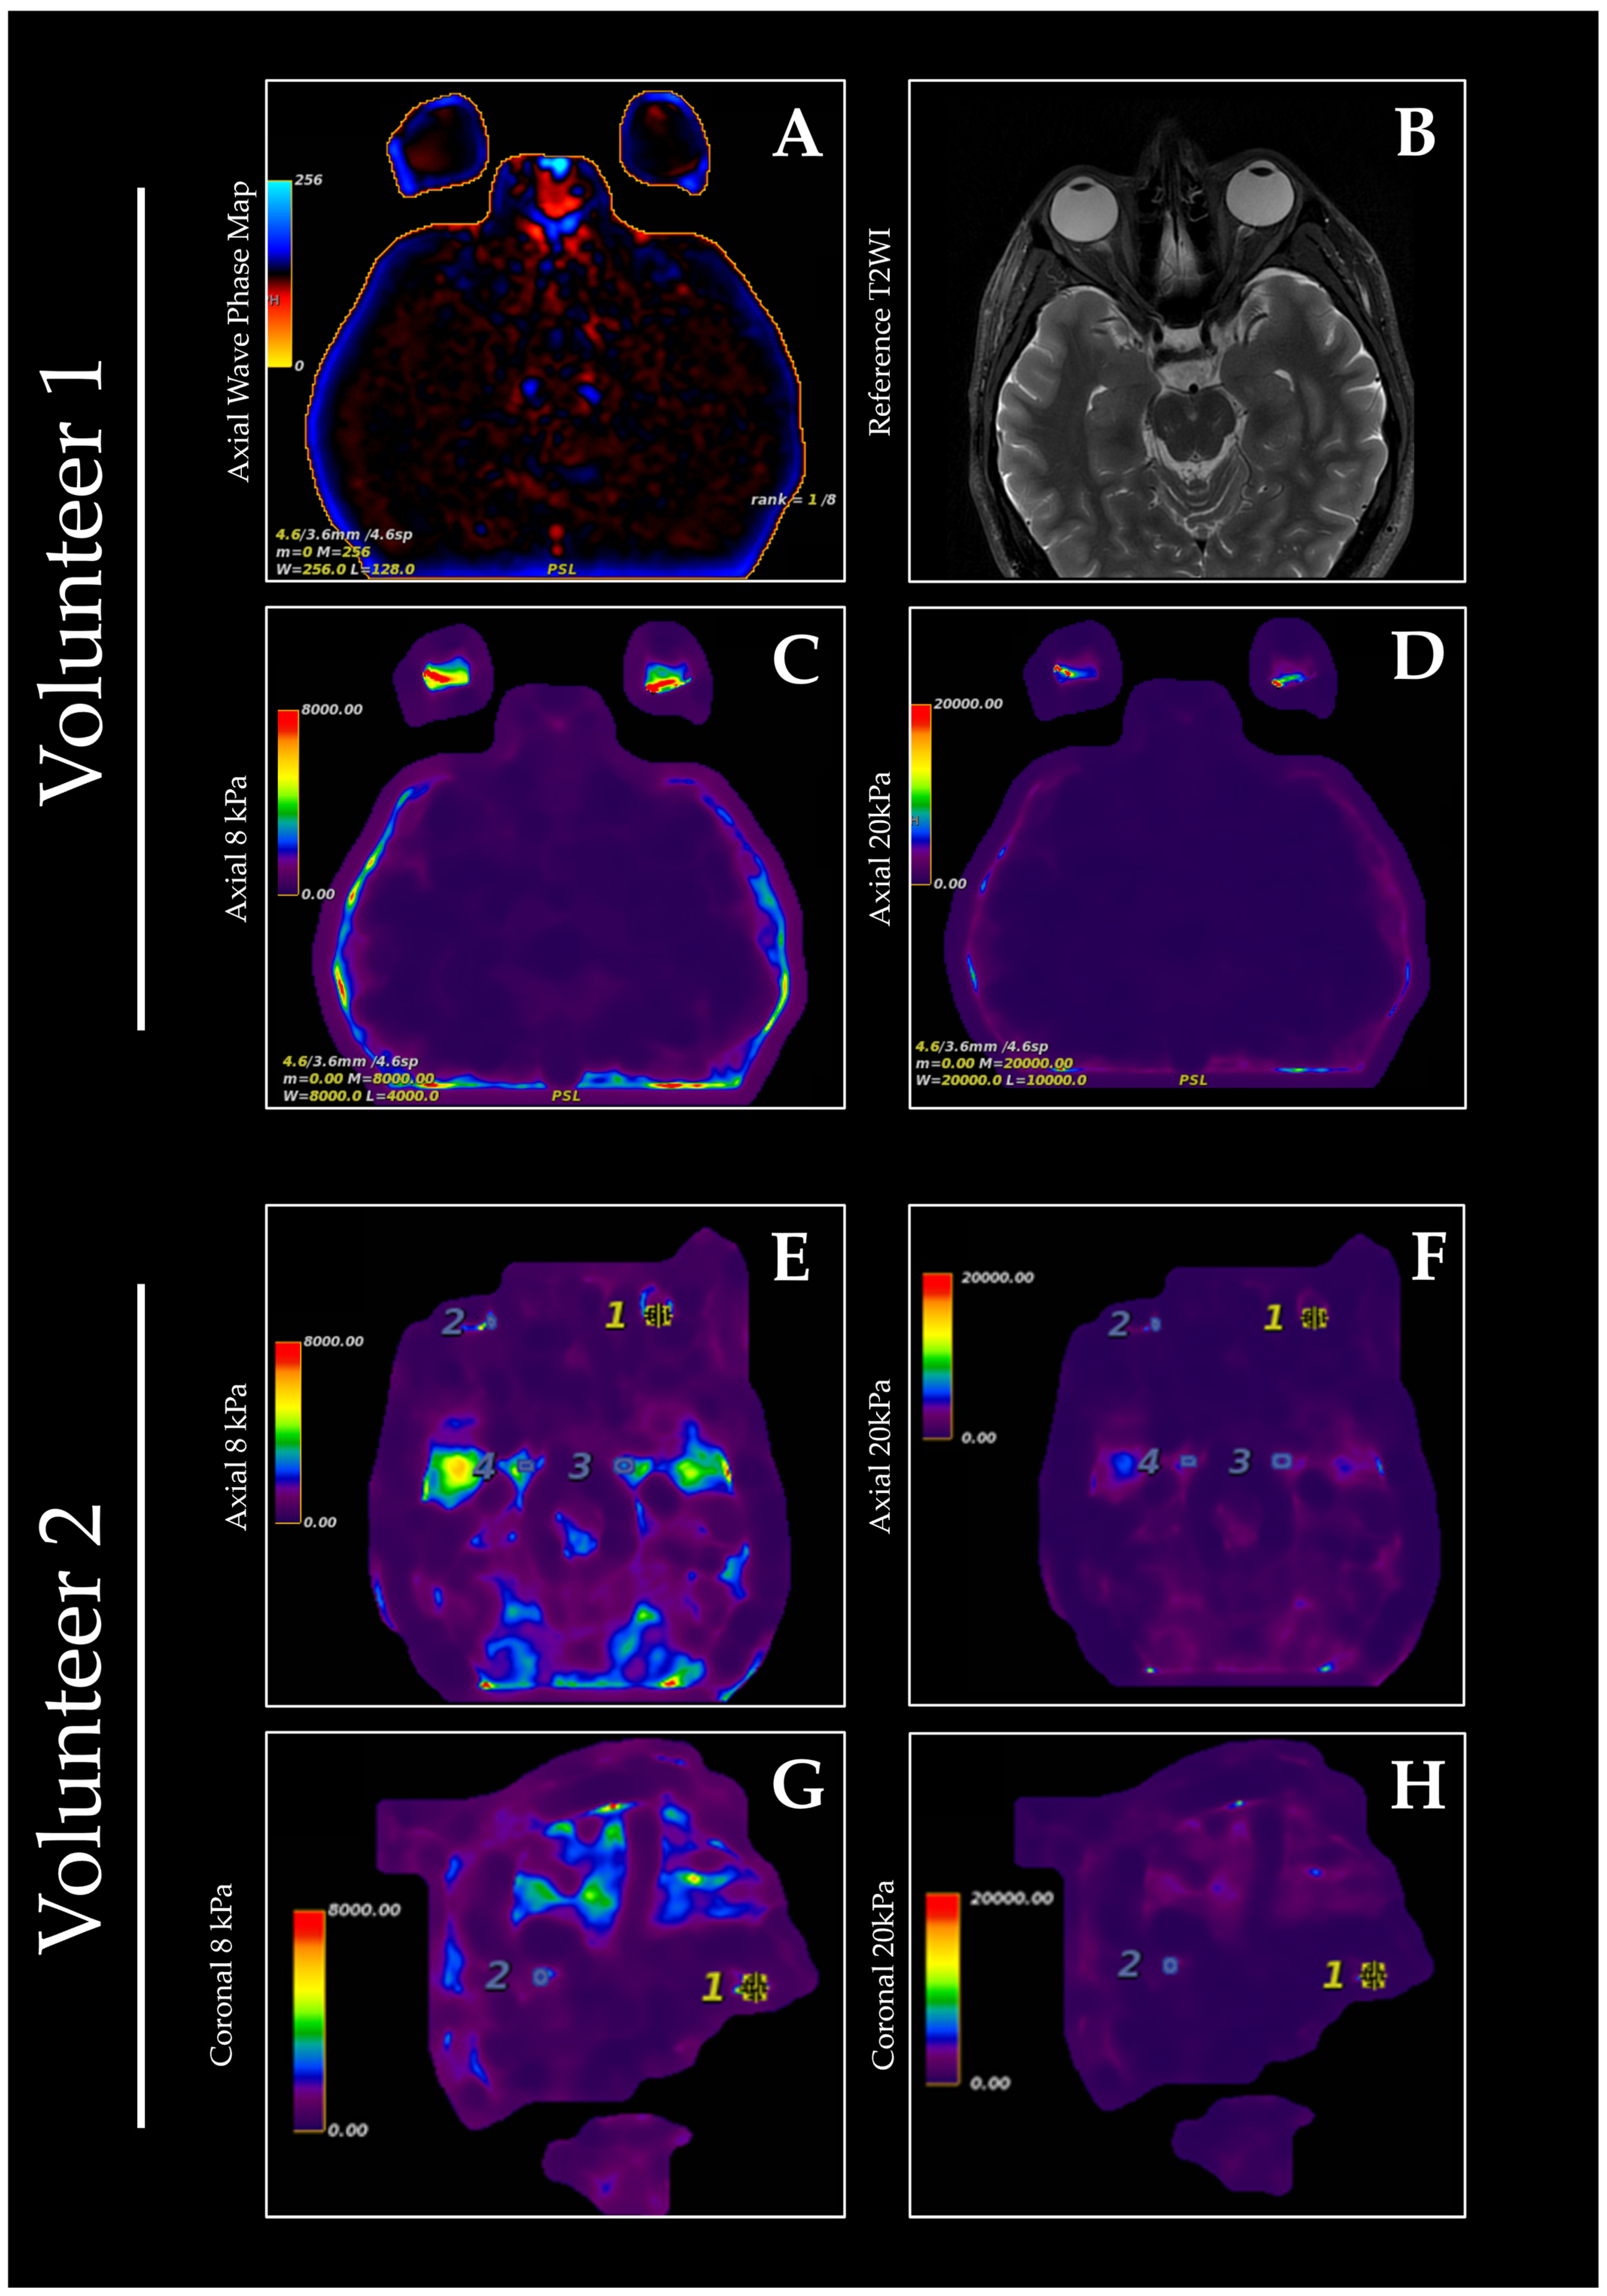

Shear Wave MR Elastography of the Orbit: Preliminary Findings